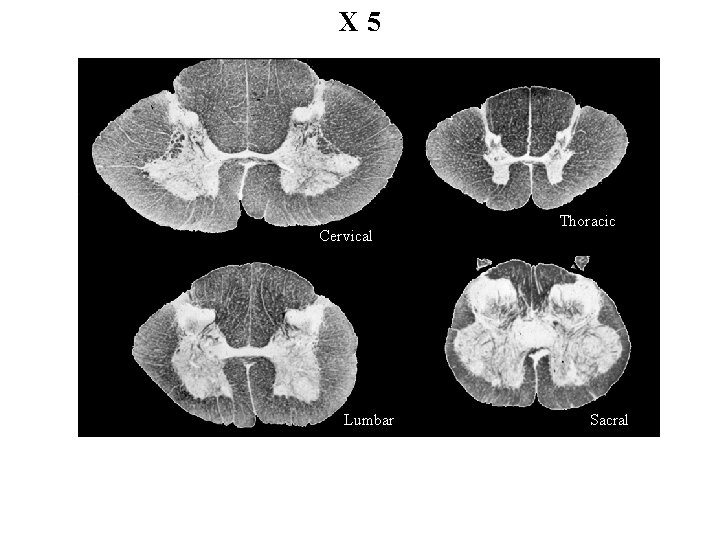

X 5 Cervical Lumbar Thoracic Sacral